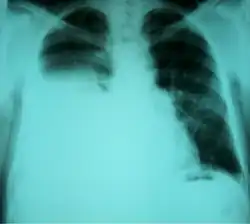

| Chest X-ray showing a hepatic hydrothorax in a person with cirrhosis | |

Hepatic hydrothorax is a rare form of pleural effusion that occurs in people with liver cirrhosis. It is defined as an effusion of over 500 mL in people with liver cirrhosis that is not caused by heart, lung, or pleural disease. It is found in 5–10% of people with liver cirrhosis and 2–3% of people with pleural effusions. In cases of decompensated liver cirrhosis, prevalence rises significantly up to 90%.[1] Over 85% of cases occurring on the right, 13% on the left, and 2% on both.[2] Although it is most common in people with severe ascites, it can also occur in people with mild or no ascites. Symptoms are not specific and mostly involve the respiratory system.